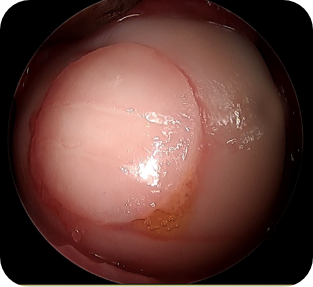

• 5) 관절경하 자가 골연골 이식술

국소부위 연골에 손상이 있는 관절염이나 연골 혈액순환의 장애가 생겨 떨어지는 박리성 골연골염 등의 환자에서 시행하는 수술 방법으로, 환자의 관절 내에 체중부하를 받지 않는 골관절 연골을 채취하여 손상부위에 이식해 주는 치료 방법입니다.

수술방법

관절경 탐색 후 손상되어 있는 연골 부분을 뼈를 포함한 원통형 모양으로 제거 후, 환자 관절 내에 체중을 받지 않는 부위의 건강한 연골부위를 같은 모양으로 채취하여 제거된 연골부위에 옮겨주는 수술입니다.

• ▲ 자가 골연골 이식술 전

• ▲ 자가 골연골 이식술 중

• ▲ 자가 골연골 이식술 후

수술장점

한 번의 수술로 결손부위를 건강한 연골로 채워줄 수 있으며, 본인의 연골을 옮겨주는 방법이기 때문에 거부반응이 없습니다. 절개 부위도 크지 않아 상처 회복에 문제가 생길 가능성이 적습니다.

수술 후 관리법

수술 후 옮겨진 골연골 부위의 유합이 일어나는 동안은 무릎을 보호해야 합니다. 수술 이후 상처가 안정화 되기 시작하는 2주째부터 보조기를 이용한 관절운동을 시작하며, 약 두 달 간은 목발을 이용한 보행을 해야 합니다.